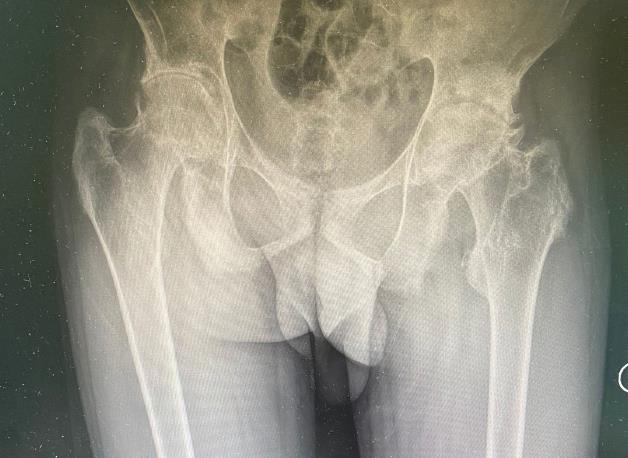

患者自述在四年前出現左髖部、左下肢外側及右髖部疼痛不適,前往當地診所行針灸理療,癥狀未見明顯好轉。近日來,患者感覺左髖部、左側膝關節及右髖部疼痛加重,在家屬的陪伴下到重慶某醫院檢查,結果顯示:腰椎普遍性骨質疏松、脊椎呈竹節樣改變、骨質硬化,考慮強直性脊柱炎。患者家屬考慮高額費用,經朋友介紹來到我院骨一科就診,門診以“1.雙側股骨頭壞死,2.強直性脊柱炎”收治入院。

患者雙下肢走路成跛行,左下肢較右下肢長約2cm,脊柱強直,側彎,病史長,目前不能正常行走,只能拄著拐杖小范圍慢慢地挪步走,嚴重影響正常生活。如果不及時進行正確的治療,病情進一步延誤,將會導致更嚴重的后果。我科主管醫生針對病人情況,考慮到此類為慢性、系統性、全身炎癥反應性疾病可累積脊柱和外周關節,治療過程中的每一個環節每一處細節都可能決定手術的成敗。手術中的操作技術,也存在一定的經驗和技巧,包括體位的擺放,兩次截骨來完成股骨側的脫位、髖臼側的定位、銼磨、以及假體的安放等。

陳主任了解病人情況后,立即組織骨科專家展開術前討論,其中表示,患者雙側股骨頭壞死,雙側髖關節骨性關節炎等并發癥,現脊柱及關節骨性強直,纖維連接明顯,現雙側髖部疼痛明顯加重(左側為重),嚴重影響生活質量,患者及家屬手術意愿強烈,診斷明確,手術指征明確,患者年輕,使用國產材料,患者活動度大的情況下,在使用大概七年左右以后需再次翻修,故國產關節不考慮使用,患者自身強直性脊柱炎,全身炎癥反應重,病情可能加重,建議行進口陶瓷對陶瓷關節假體。術前準備已完善,故定于5月30在全麻下行左側全髖關節置換術,待病情穩定后再次行右側髖關節置換術。

術后復片